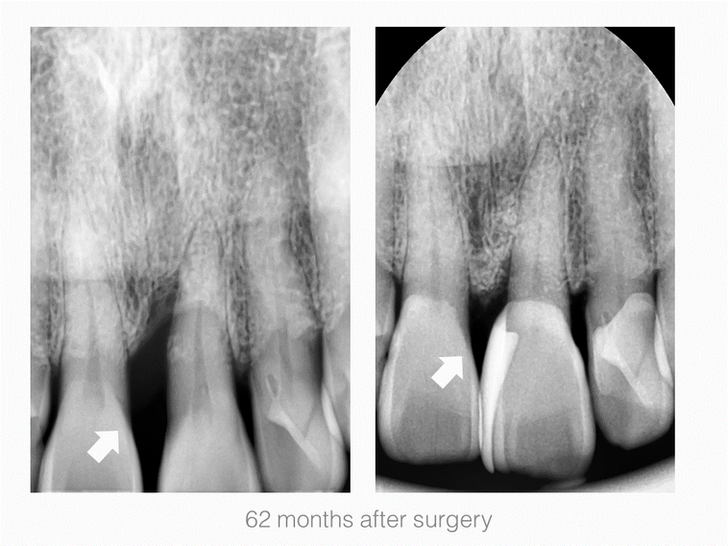

2. Maxillary Lateral incisor

3. Maxillary Central incisor